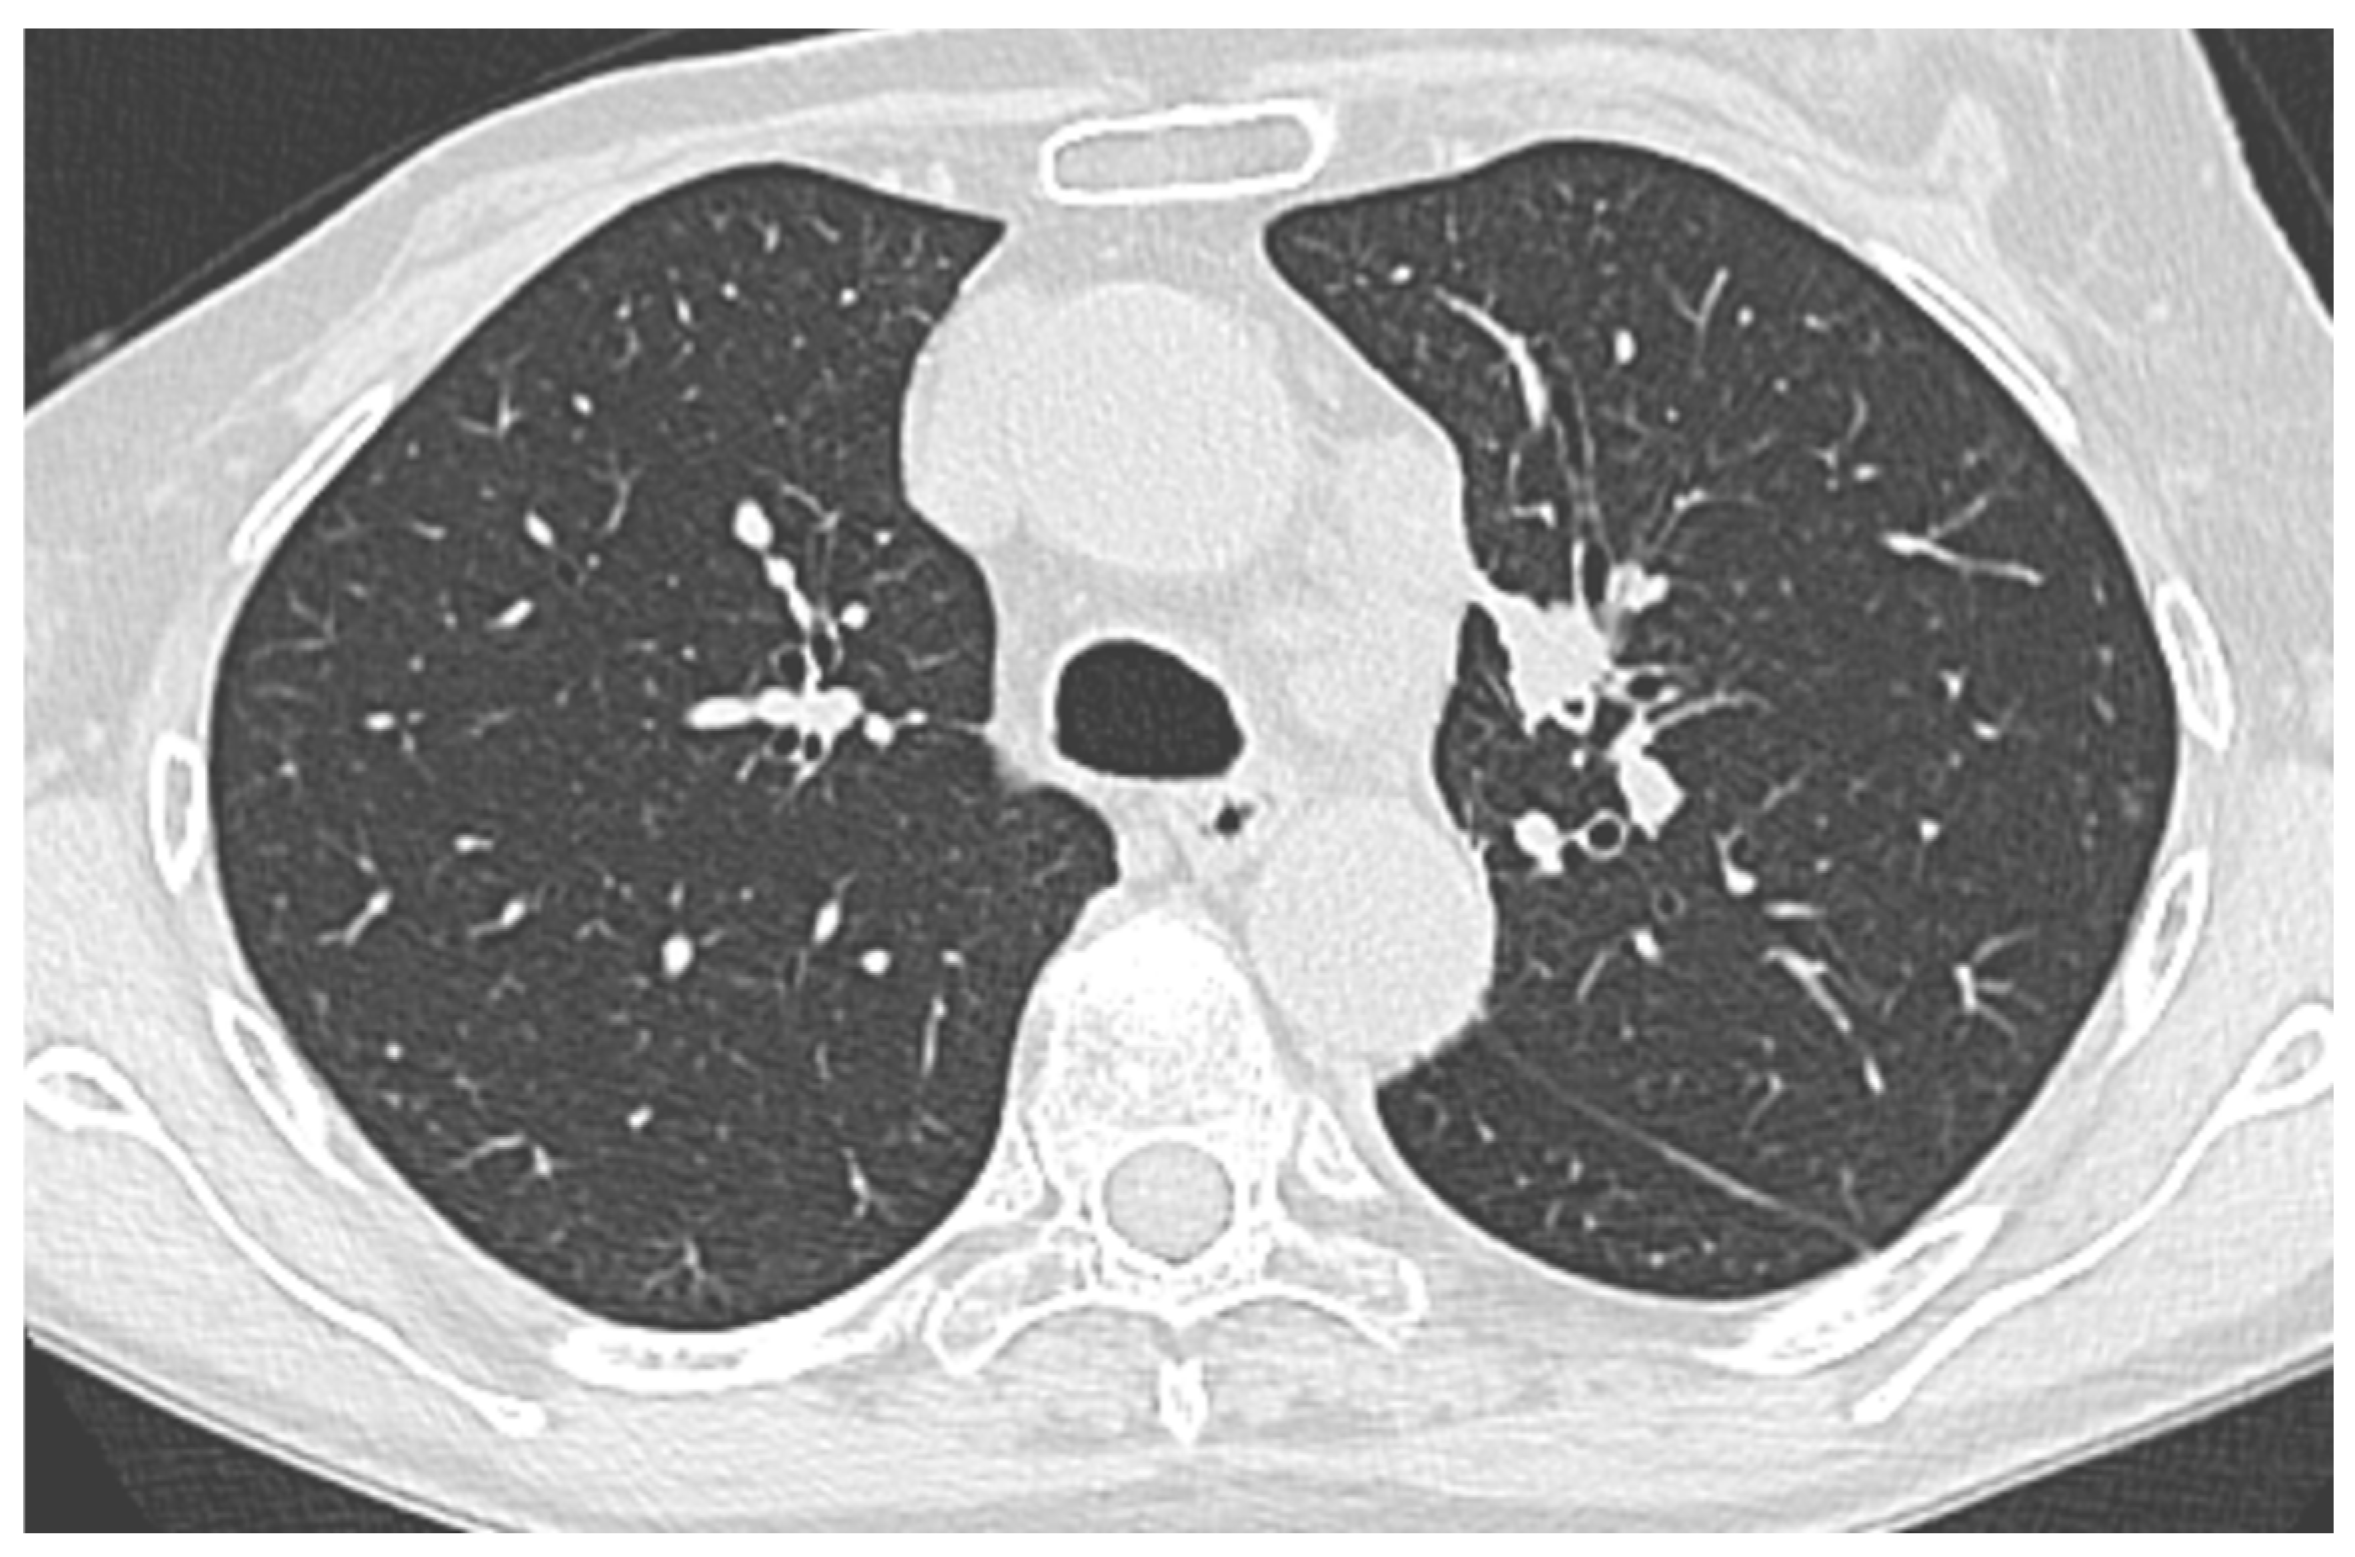

Figure 2. Chest CT scan example of a peripheral pulmonary lesion (PPL) sampled with a thin bronchoscope (TB).

Bronchoscopy with a TB was performed under moderate sedation using our institution’s standard protocol. Patients were monitored during all parts of the procedure and sedation was titrated to the patient’s comfort and ability to follow commands. A TB was used (EB-710P, Fujifilm, Tokyo, Japan), shown in Figure 1. Target tool identification was used at the discretion of the bronchoscopist, depending on the endoscopic finding and chest CT scan imaging (R-EBUS, R-EBUS + fluoroscopy, none), shown in Figure 2 and Figure 3. The target lesion was sampled with 2.00 mm forceps (Endojaw FB-211D, 1.9 mm, Olympus Medical Systems Corp., Tokyo, Japan) or with a conventional TBNA needle (Wang® Transbronchial cytology needle MW-122, Conmed, Utica, NY, USA).